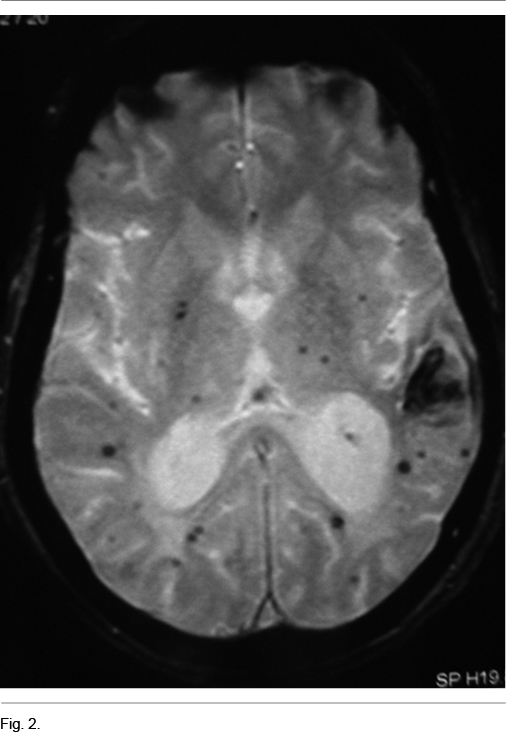

Se planteó síndrome demencial rápidamente progresivo (DRP) y solicitó RNM que muestra múltiples imágenes anormales de diferentes tamaños a nivel subcortical y cortical, hipo intensas en T1 híperintensas en T2, que corresponden a pequeñas hemorragias corticales y subcorticales evolucionadas (Figuras 1 y 2).

La AAC debe ser sospechada clínicamente en pacientes mayores de 60 años con hemorragias cerebrales múltiples en ausencia de una causa evidente (5). En la Resonancias Magnética Nuclear (RNM) es característica la presencia de imágenes compatibles con microsangrados difusos como en este paciente, así como depósitos de hemosiderina.